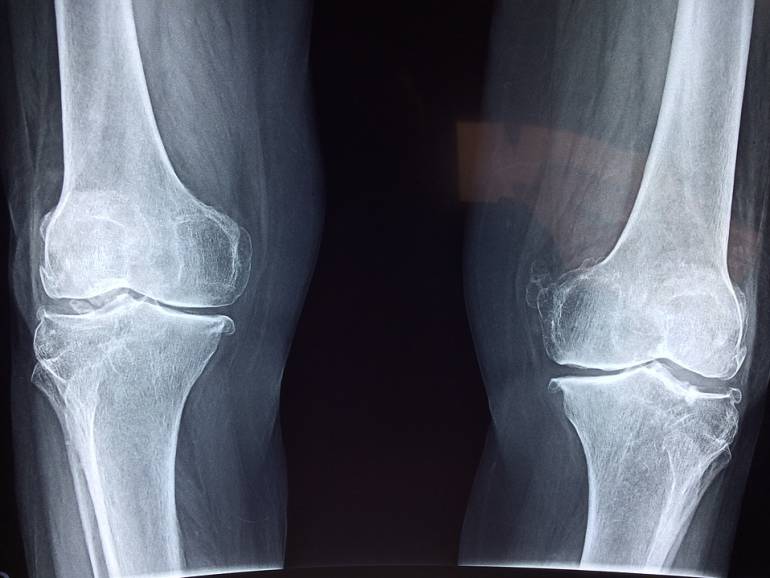

(C.C Google Images Pixabay)